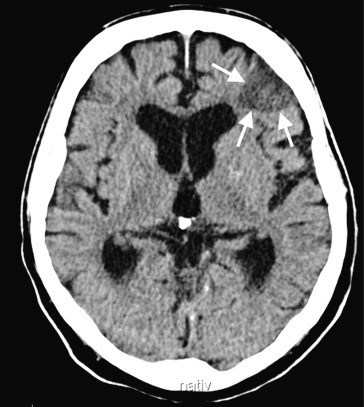

Mit transportablen Blutdruckautomaten gelingt eine objektive Erfassung des Blutdrucktagesprofils, das zur Beurteilung des Schweregrades der Hypertonie und des Therapieeffektes von großem Nutzen ist. Es schützt auch davor, einen erregungsbedingten „Sprechstundenhochdruck“ zu missdeuten und falsch zu behandeln. Beim ambulanten Blutdruckmonitoring (ABDM) wird der Blutdruck in halb- bis einstündigen Intervallen über 24 h gemessen. In der Nacht sinkt der Blutdruck normalerweise deutlich ab. In ◘ Abb. 1.4 ein normales, in ◘ Abb. 1.5 ein pathologisches ABDM wiedergegeben.